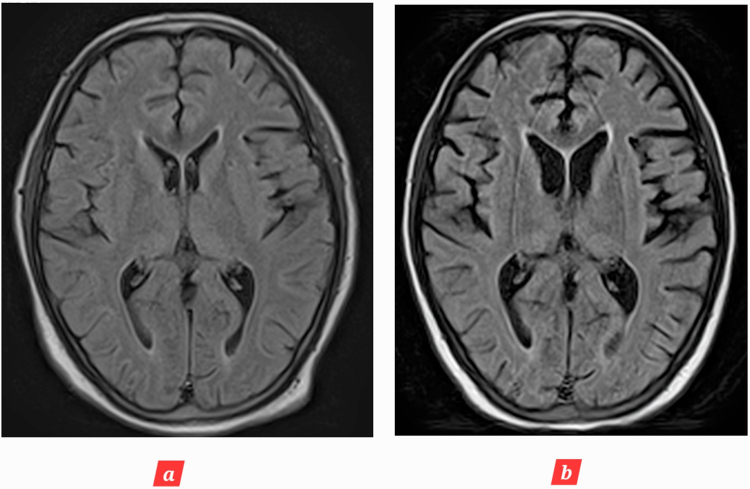

Introduction and importance: Age-inconsistent brain atrophy refers to brain shrinkage that is not proportional to chronological age. This case report is first to report a young patient who developed age-inconsistent brain atrophy due to post cardiac arrest brain injury (PCABI). Due to limitations in the available data, we report our experience and novel magnetic resonance (MR) imaging changes in the brain over the course of 2 months.

Case presentation: We report a case of a 28-year-old woman who developed sudden cardiac arrest during a routine cesarean section, with loss of consciousness for an unspecified period of time. She was resuscitated, intubated and later transferred to intensive care unit (ICU); where her Glasgow Coma Scale on arrival was 4/15. Detailed history, physical examination, and radiological investigations confirmed the diagnosis of PCABI. She was treated in ICU along with physiotherapy for speedy recovery.

Clinical discussion: PCABI is the major cause of long-term disability and mortality following cardiac arrest. In this novel case report, we establish that it can lead to age-inconsistent brain atrophy.

Conclusion: Serial MR imaging scans of the brain should be performed for suspected or confirmed PCABI to evaluate brain atrophy and other changes. This will not only aid in deciphering residual brain deficits but also help in guiding the correct management of the patients.